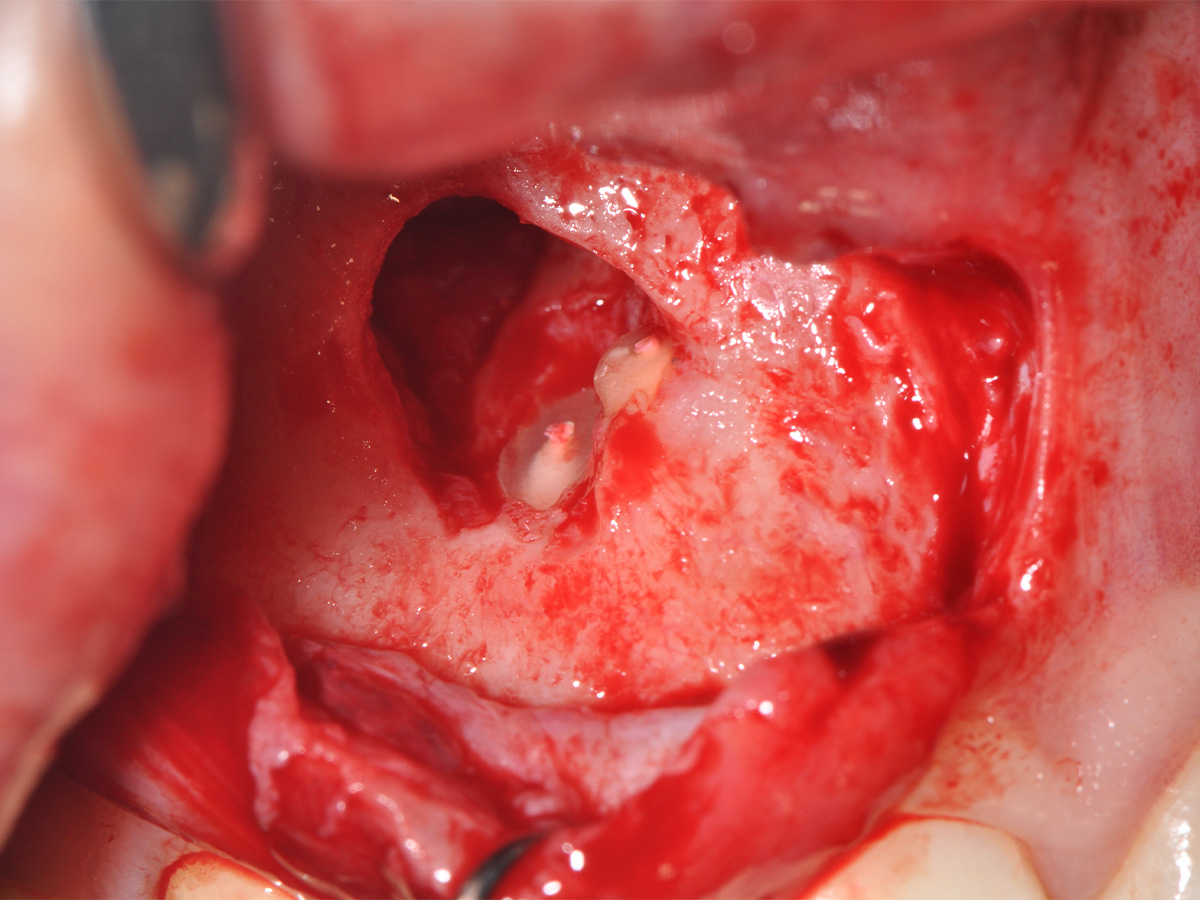

Abbildung 10

Nach vestibulärer Freilegung wurde die Zyste vollständig entfernt und zur histopathologischen Untersuchung eingesandt.

Abbildung 11

Anschließend erfolgte eine Wurzelspitzenresektion an den Zähnen 11 und 12 durch die vestibuläre ossäre Perforation, gefolgt von einer ultraschallbasierten, retrograden Kanalaufbereitung und Abdichtung mit MTA.

Mit der Patientin wurde der Versuch des Zahnerhaltes trotz ausgedehnter Zyste besprochen. Gleichzeitig sollte das Zystenlumen zu einer sicheren ossären Durchbauung geführt werden, um eine implantologische Sofortversorgung vorzubereiten, falls zu einem späteren Zeitpunkt eine Zahnentfernung notwendig werden sollte. In der Phase vor der geplanten Operation wurden die Wurzelkanalfüllungen an Zahn 11 und 12 durch einen Endodontologen alio loco revidiert. Die Schnittführung wurde aufgrund des bestehenden „Gummy Smile“ hoch im Vestibulum geführt – so konnte die delikate Parodontalstruktur in ihrer Form unangetastet belassen werden, um einen möglichst optimalen ästhetischen Erfolg zu erreichen (Abb. 8, 9). Nach vestibulärer Freilegung wurde die Zyste vollständig entfernt und zur histopathologischen Untersuchung eingesandt (Abb. 10). Anschließend erfolgte eine Wurzelspitzenresektion an den Zähnen 11 und 12 durch die vestibuläre ossäre Perforation (Abb. 11), gefolgt von einer ultraschallbasierten, retrograden Kanalaufbereitung und Abdichtung mit MTA. Um die knöcherne Durchbauung am Boden der Zyste osteoinduktiv zu unterstützen, wurden mit Hilfe eines mechanischen Knochenschabers aus dem Bereich des rechten naso-palatinalen Pfeilers Knochenchips entnommen und als erste basale Augmentationsschicht in den ossären Defekt eingebracht (Abb. 12). Der größere Anteil von 80 % des Defektvolumens wurde mit einem vollständig resorbierbaren, xenogenen Augmentationsmaterial aufgefüllt (Abb. 13) (mp3®, OsteoBiol®). Der Defekt wurde zum Vestibulum hin mit einer stabilen, vollständig degradierbaren Membran abgedeckt (Abb. 14) (Soft Cortical Lamina, OsteoBiol®). Zum einen wurde hiermit im Sinne der GBR das Weichgewebe vom Augmentat getrennt. Zum anderen verhinderte die stabile Membran das Einwachsen eines Weichgewebeankers in den Defekt und damit eine narbige Verziehung im Vestibulum. Um eine Verschiebung der Membran zu vermeiden, wurde diese mit zwei Titanpins in der Kortikalis fixiert. Die Pins wurden bei Beschwerdefreiheit in situ belassen (Titan-Bone-Pin-System). Der Wundverschluss erfolgte einschichtig mit nicht resorbierbarem Nahtmaterial (Abb. 15) (Seralene® 5-0 DS-15). Peri- und postoperativ wurde eine antibiotische Abschirmung unter Fortführung für insgesamt drei Tage mit Amoxiclav 875/125 1-0-1 durchgeführt.